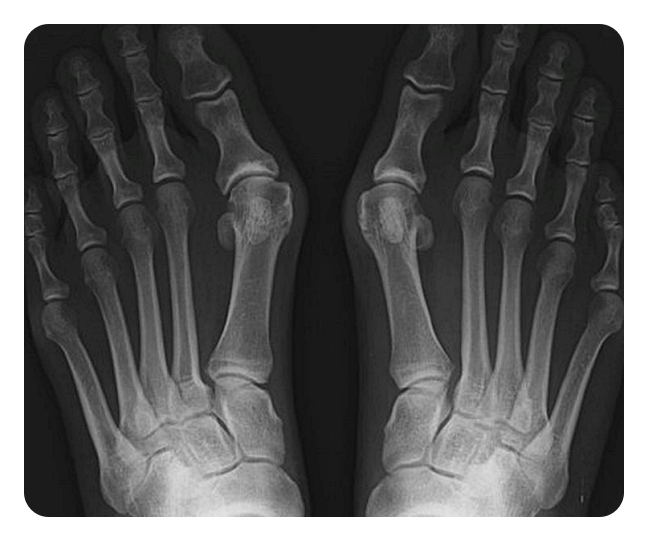

신발에 자극을 받아서 발가락이 두꺼워지면, 그 다음으로는 두 번째, 세 번째 발가락에도 영향을 주게 되며, 결국 피부 관절이 탈구되기도 합니다. 외형적 변형만 봐도 쉽게 진단할 수 있습니다. 하지만 치료 방향성을 결정하기 위해서는 방사선 찰영상 검사가 필요할 수 있습니다. 대부분 발에 체중이 실린 상태에서 찰영상을 진행하게 되고, 과학적으로 측정하여 관절의 변화를 관찰하게 됩니다. 의사는 엄지발가락의 관절 돌출 정도, 겹침 정보, 관절 자체의 통증 여부, 전체적인 관절의 유연성 여부 등을 검사하게 됩니다.